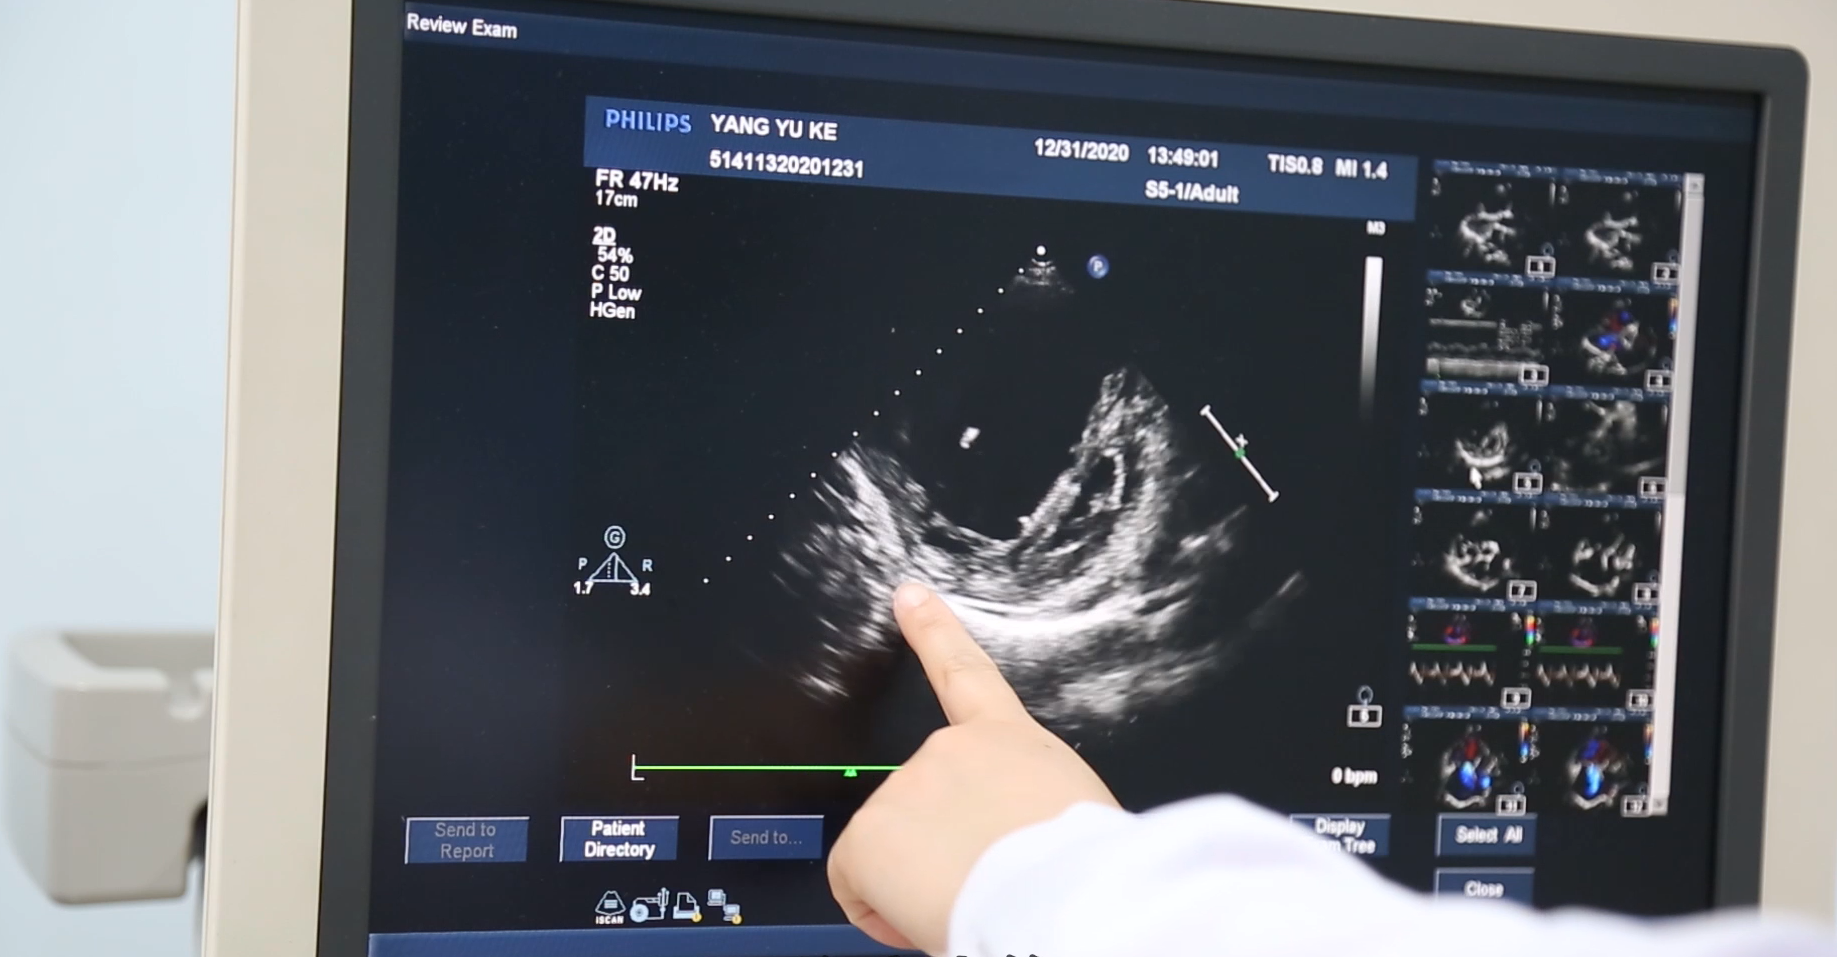

A1:心脏超声能够利用超声波扫查,透过人体骨骼和皮肉对心脏结构、搏动以及血液流动等情况进行观察,明确心室、大血管的功能情况以及完整性它没有放射性和毒性,是一种无创性检查技术。超声波一开始被用于军事领域,现伴随科技发展,进入医学领域为守护人类身体健康发挥重要作用。

心脏是全身血液流动的泵,它有四个心腔,有5组大血管进出心脏,心脏超声主要是检测心脏和大血管结构、功能及血流的变化,对于心脏病患者的诊断、治疗决策、疗效评价及指示预后具有非常重要的意义。

威海市立医院心脏超声科现有4台世界高端超声诊断仪和1台便携式心脏彩超仪,其中两台是PHILIPS iE33世界高端超声诊断仪,另外更先进的两台是PHILIPS EPIQ5世界高端超声诊断仪,还有一台是国产迈瑞M9便携式心脏彩超仪。